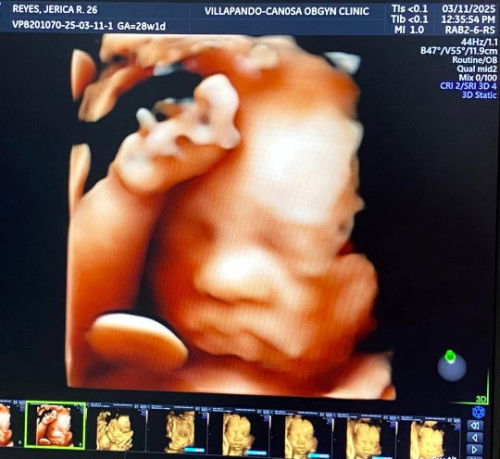

ultra sound

worth it eto naman yung baby namin ❤ 1750 lang depende kasi sa package with one printed pic, video and pic sa cp ko ng ibang anggulo niya.

Here's mine. 🤗 4D ultrasound. 3,600 dito sa amin. ❤️ mas nakaka excite makita na healthy si baby at nakaka idea simpng kamukha 🥰